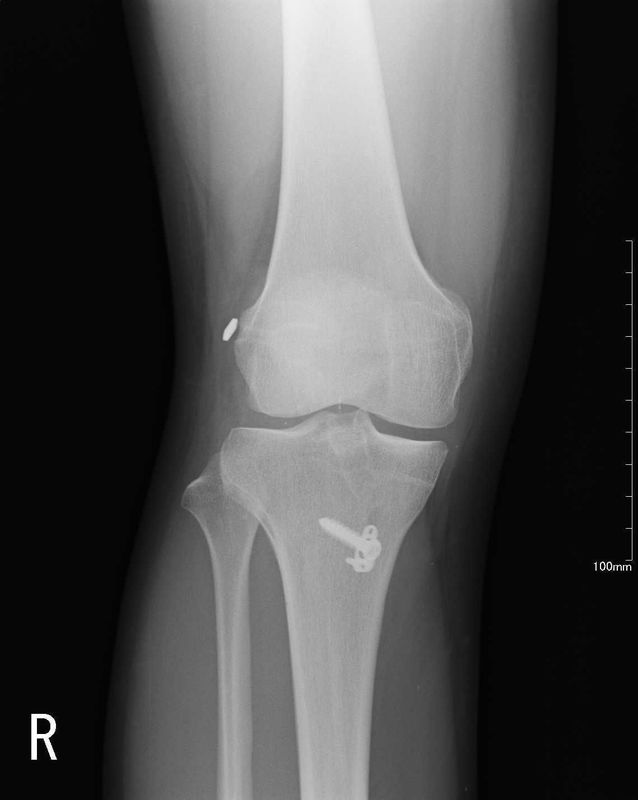

術後画像

| レントゲン | MRI |

| 異常なし | 再建靭帯の成熟をみとめる |